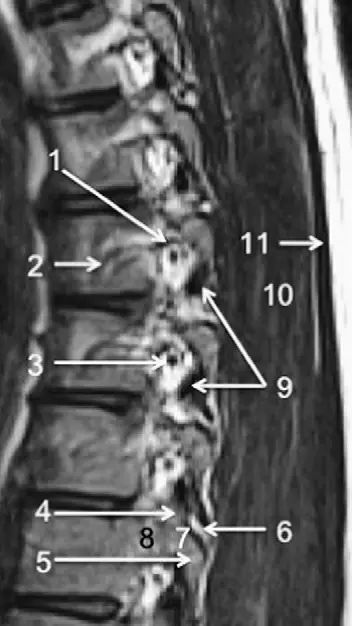

脊柱的MRI解剖

3、MRI:可显示骨折所致血肿及脊髓损伤所表现出的异常高信号。(平扫)